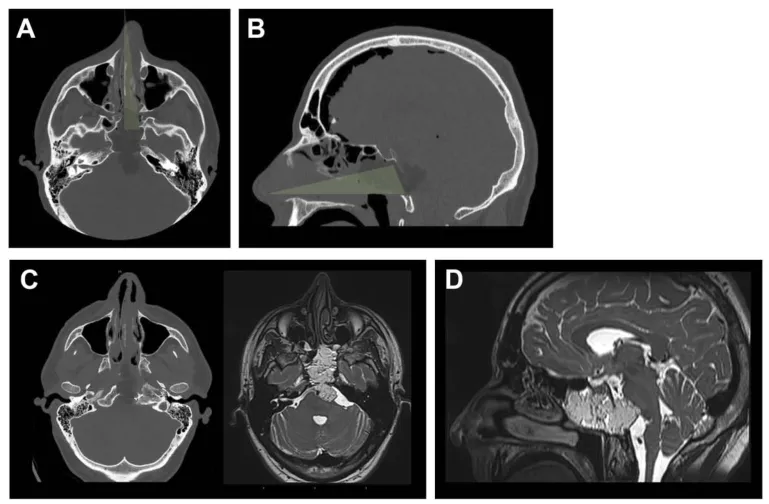

图3. 术后影像及结果。A和B,术后计算机断层扫描的轴位和矢状位视图,展示了保留鼻腔完整性的单鼻孔目标性入路。鼻中隔、上颌窦、后组筛窦及左侧蝶窦间隔保持完整。C,为显露肿瘤外侧部分,磨除了左侧颈静脉结节。D,蝶窦被颅腔化并用自体脂肪填充,同时缝合了头端黏膜。实现了肿瘤全切,且未检测到脑脊液漏。

术后管理方面,患者床头抬高45度,术后第一天即开始活动,两周内避免平卧。为预防脑脊液漏,在局部麻醉下共进行了3次腰椎穿刺脑脊液引流。抗生素使用持续48小时。术后未出现神经功能缺损、脑脊液漏或感染,患者于一周后出院回家。术后一周进行了计算机断层扫描和磁共振成像检查,术后第二个月进行了第二次磁共振成像检查——两项检查均有所推迟,目的是避免成像过程中过早平卧。两次检查均证实肿瘤被完全切除。